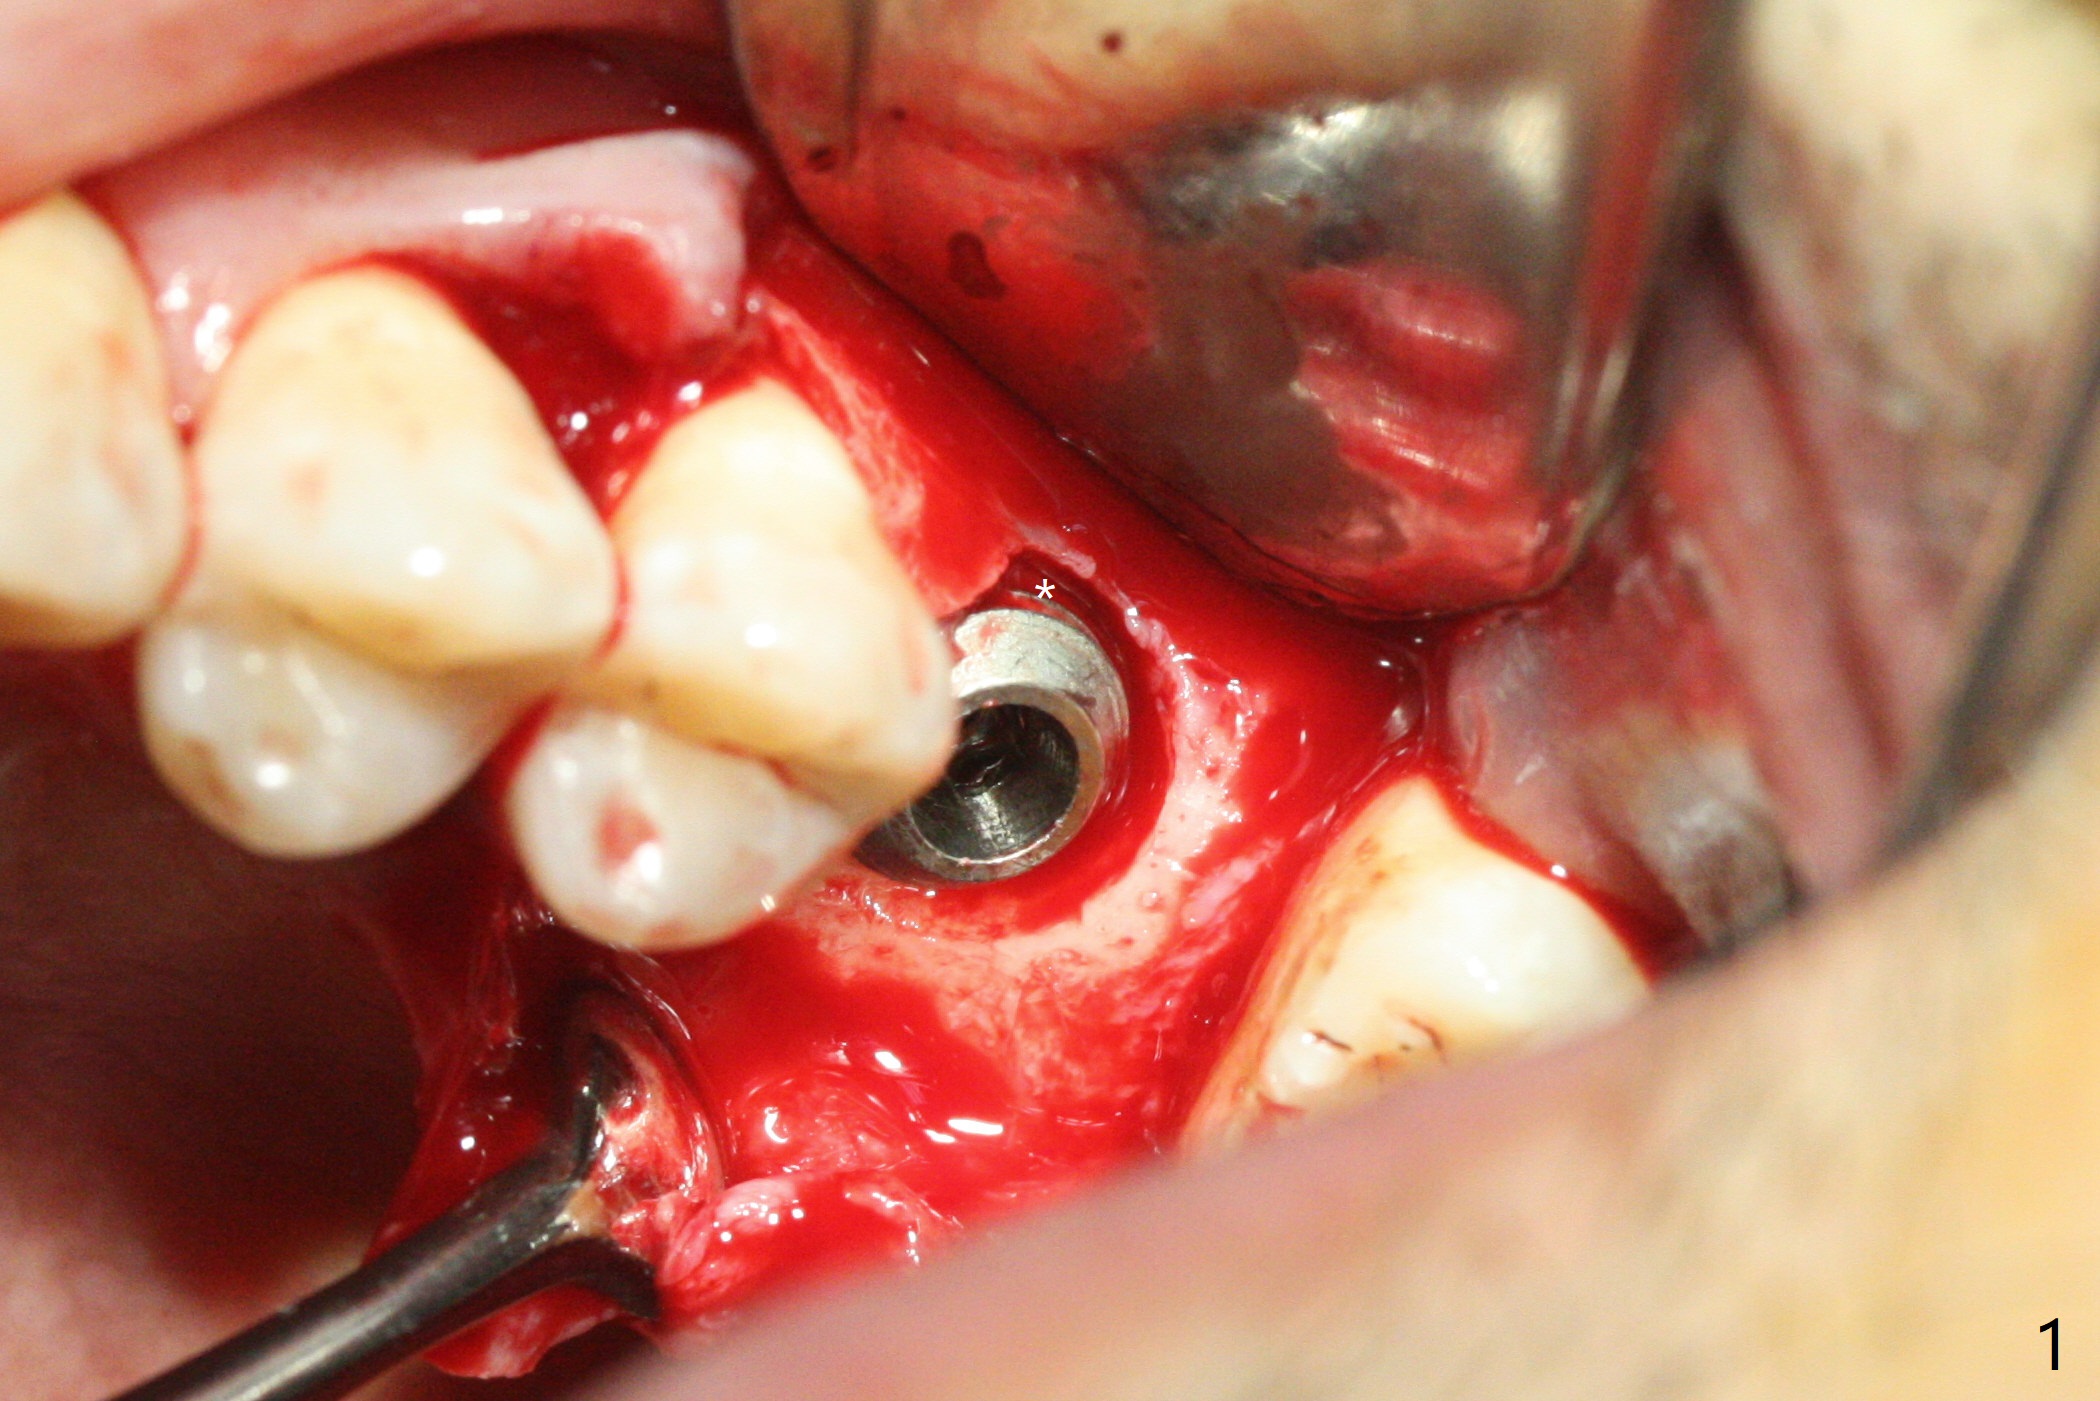

When the crown and abutment at #14 are removed, the implant is found to be shallowly placed. Upon incision, the implant threads are exposed circumferentially and coronal to the buccal crest (Fig.1 *). It seems to be difficult to expect bone regeneration post bone graft. The implant (6.4x6 mm) is removed with a 7/8 mm trephine bur, followed by sticky allograft (Fig.2 *), PRF membrane and 6-month membrane. In spite of the setback, the bone height increases from 3.9 mm to 11 mm due to sinus lift associated with the previous implant placement (Fig.2 L). The depth of the 2nd placement will be controlled by surgical guide. When the periodontal dressing dislodges 11 days postop, the 6-month membrane is lost as well as part of the bone graft. If there is remaining apical native bone, an immediate implant should be placed so that bone graft can be kept in place more securely with an immediate abutment and provisional! The seemingly conservative approach is actually not safe. The wound heals 1 month postop (following dislodgement of the 2nd periodontal dressing, Fig.3). Three months later, consider using bone expanders to do sinus lift and place a SM implant subcrestal. Take PA after 1st expander to the depth. The wound heals 4 months postop (Fig.4), but the bone height (Fig.5) and width (Fig.6) decreases. The latter continues to decrease 9 months postop (Fig.7,8), but bone density is high, average 1360 units. Preparation includes guide, incision, sinus lift, implant placement (possibly tissue-level (9) or FC if the sinus membrane perforates), bone graft, and suture.